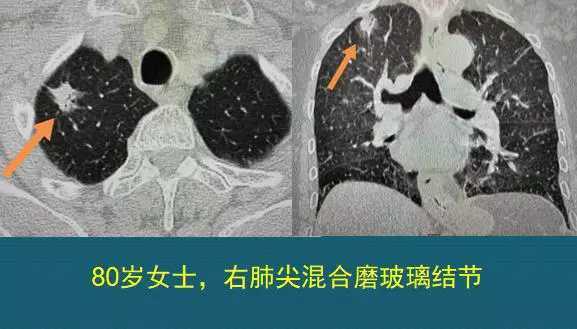

4.混合磨玻璃结节,边缘有清晰的磨玻璃影,同时伴有胸膜牵拉。

下图这一例就是典型的肺腺癌,它的恶性征象有:形态不规则、表面分叶、肺门侧可见小血管进入、内部实性成分不规则、病灶边缘有清晰的磨玻璃影,伴有胸膜牵拉。